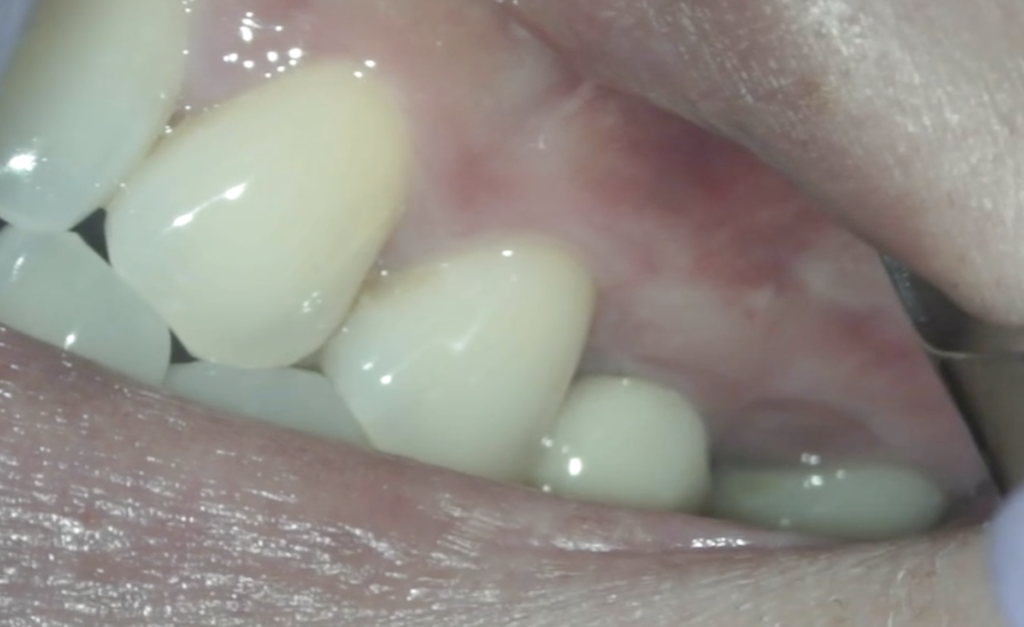

歯肉の腫脹は消失した。

そして歯肉はどうだろうか?